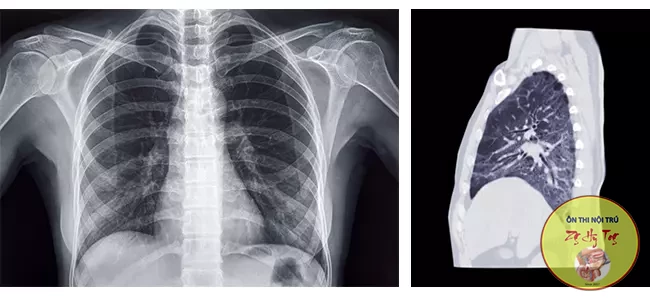

- Khi nhìn giấy ra viện thì thấy mẹ chị chẩn đoán K phổi giai đoạn 4, giải phẫu bệnh là ung thư biểu mô tuyến, xét nghiệm đột biến EGFR không phát hiện đột biến, điều trị qua rất nhiều phác đồ hoá chất nhưng bệnh tiến triển gây tràn dịch làm “trắng xoá” một bên phổi phải. Do thể trạng gầy yếu, khó thở đặc biệt khi gắng sức cần hỗ trợ oxi, bản thân đã điều trị qua tất cả các phác đồ hoá chất được khuyến cáo, bs Cường khuyên gia đình mượn mẫu bệnh phẩm ở bệnh viện X xét nghiệm đột biến đa gen. Điều may mắn là mẹ em có tái sắp xếp ALK, một loại đột biến đáp ứng tốt với điều trị.

- Có em bệnh nhân K phổi di căn não đa ổ, ALK (+) đến khám định kì, kết quả rất khả quan: Từ di căn não đa ổ, ổ lớn 5cm gây đau đầu mờ mắt, sau 6 tháng điều trị Alectinib 4v/ngày thì hết tổn thương. U phổi trái chỉ còn dải xơ sẹo. Em gái hỏi mình: Em có kết quả tốt thế này thì dừng thuốc đích 1-2 tháng được không?(áp lực kinh tế). Tế bào ung thư này như cái bọn khủng bố, khi nhà nước đàn áp nó núp dưới hầm trú ẩn. Khi hết đàn áp thì nó ngoi lên và càng lộng hành, tàn bạo hơn.